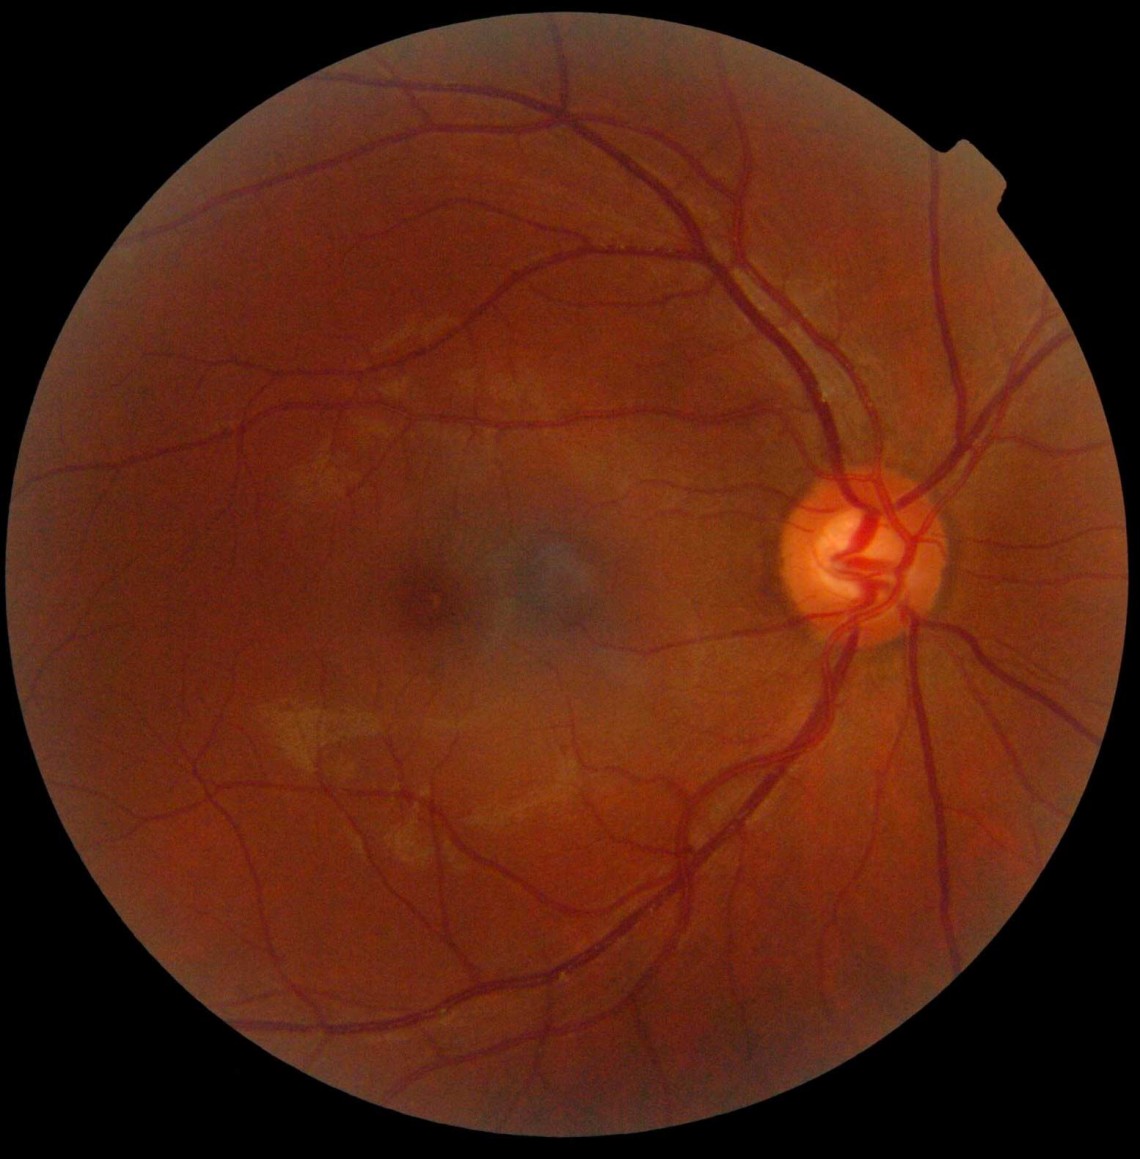

Слой Дюа

В ходе другого исследования учёные обнаружили ранее неизвестный слой в человеческом глазу.

Это тонкая, прочная структура, получившая в честь своего первооткрывателя название «слоя Дуа», толщина которого составляет всего 15 микрометров, или одну миллионную часть метра, и находится за роговицей.

Открытие этого слоя поможет исследователям лучше понять некоторые заболевания глаз, которые могут быть вызваны разрывом или травмой этого слоя.